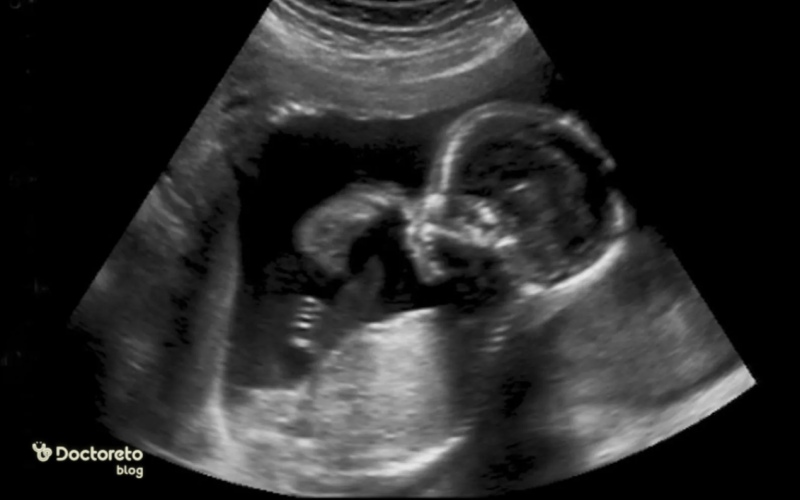

در هفته چهاردهم، جنین حدود ۸.۵ تا ۱۰ سانتیمتر قد و ۴۰ تا ۶۰ گرم وزن دارد. گردن جنین مشخصتر شده، سلولهای قرمز خون تشکیل میشود و اندامهای جنسی رشد کردهاند. جنین حرکات صورت مانند مکیدن انجام میدهد اما مادر هنوز احساس نمیکند. کلیهها ادرار تولید میکنند و موهای نازک ظاهر میشود. سونوگرافی میتواند ضربان قلب را نشان دهد. جنین در مایع آمنیوتیک شناور است و رشد سریع دارد.

حرکات جنین در هفته چهاردهم

حرکات جنین در هفته چهاردهم شروع شده اما مادر معمولا تا هفته ۱۶ تا ۲۰ احساس نمیکند. جنین مشت میزند و عضلات صورت را تمرین میدهد. این حرکات برای رشد عضلانی ضروری است. سونوگرافی میتواند حرکات را نشان دهد.

سونوگرافی در هفته چهاردهم بارداری

جنسیت ممکن است در سونوگرافی هفته ۱۴ دیده شود اما با احتمال خطا (تا ۲۰ درصد)؛ برای دقت بیشتر از هفته ۱۶ یا NIPT استفاده کنید. سونوگرافی بعدی معمولا در هفته ۱۸ تا ۲۰ برای بررسی آناتومی انجام میشود.